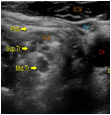

Live Model Station Demonstrate / Practice

• US scanning technique

• Sono-anatomy

• US image optimization

• Sono-anatomy and Practice Block Technique

• Needle tracking